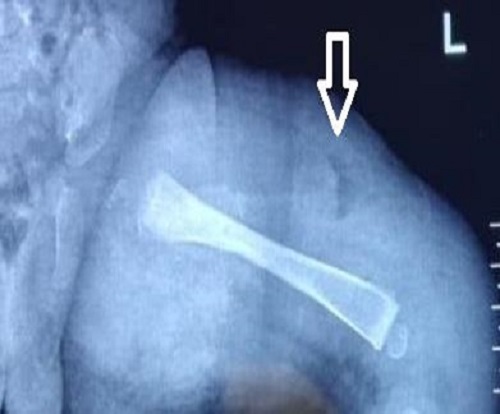

Figure 1

X-ray showing periosteal elevation of femur suggestive of subperiosteal collection.

A 28-day old male neonate presented to emergency with a complaint of swelling left thigh for 7 days which increased over the last 3 days. There was a history of fever for 2 days and reddish discoloration of thigh skin for the last 2 days. The baby had decreased oral intake for 1 day. There was no history of trauma or massage. On examination, the baby was febrile with a heart rate of 138/min and had restricted movement of the left lower limb. Signs of inflammation were present. The baby was fluid resuscitated and routine sampling revealed Hb 12 gm/dL, total leucocytes count (TLC) of 17500/uL with neutrophils of 72 %, C-reactive proteins (CRP) were 332 mg/L and platelets of 1.6 lakhs/uL. Other blood parameters were normal except for high K levels (> 7 mmol/L). Supportive treatment was started for hyperkalemia and i.v. antibiotics [Cloxacillin, Amikacin as per hospital policy] started after sending blood cultures. X-ray left lower limb (LL) was done and revealed soft tissue edema and hypertrophy but no bony changes. The baby was kept on conservative management with i.v. antibiotics, limb elevation, and local hygroscopic measures to relieve tissue edema. Meanwhile, the baby developed swelling of the whole lower limb, though TLC and CRP were decreasing. In view of the deterioration of clinical condition, the baby planned for fasciotomy after 5 days and multiple fasciotomies of left LL were done [1 incision on thigh lateral aspect, incision each on medial and lateral calf, and 1 incision on dorsal foot]. It drained the intramuscular fluid and showed ischemic changes in the medial calf area but no pus was found. It led to clinical response in the calf area in the postoperative period. Blood culture revealed Methicillin-resistant Staphylococcus aureus (MRSA) and antibiotics were changed to vancomycin. The baby had improved in general condition. Thigh swelling had little response and the X-ray was repeated which showed periosteal elevation (Fig. 1). The baby underwent surgical drainage and around 50 ml of thick pus was drained. Pus culture also showed MRSA growth. The baby was discharged on oral linezolid after 1 week of i.v antibiotics. At 2 years and 7 months, the baby is asymptomatic and able to walk with support.